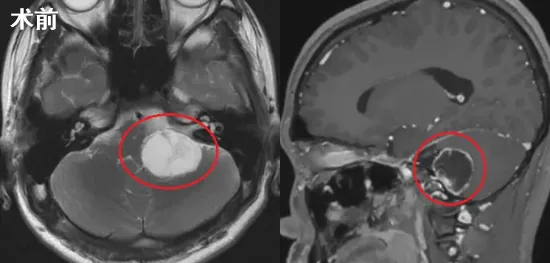

直至在另一家医院进行核磁共振检查,真相才得以揭示:CPA区和颈静脉孔区发现一个体积较大的肿瘤!

尽管年仅15岁,沫沫已具备为自己人生负责的能力。影像学显示肿瘤位于颈静脉孔区,沿舌下神经管区走行,边界清晰,最大横断面约2.4cm×2.0cm,左侧小脑半球和脑干轻度受压。